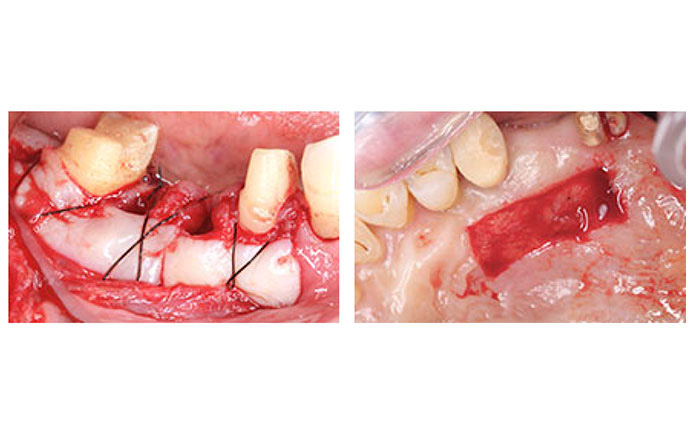

6.状態の悪い歯ぐきの形成を行う、遊離歯肉移植術(FGG)

遊離歯肉移植術(FGG)は、歯ぐきが下がって、歯が長くなってしまっている場合や、お掃除しにくい歯ぐきの形の改善を目的として行う手術です。

遊離歯肉移植術は、硬いぐきが少ない、お掃除しにくい歯ぐきの形の改善を目的として行われます。

手術部位を開き、上顎の歯ぐきから上皮と言われる組織のついた歯ぐきを採取し、移植したい部分に移植します。

1)遊離歯肉移植術(FGG)を行うメリット

・一度の手術で広範囲の処置が可能

・お掃除がしやすい歯ぐきの状態にできる

2)遊離歯肉移植術(FGG)を行うデメリット

・手術部位が2箇所になる(移植する部位と歯ぐきを取ってくる部位)

・移植した歯ぐきの色などが周囲と違うことがある